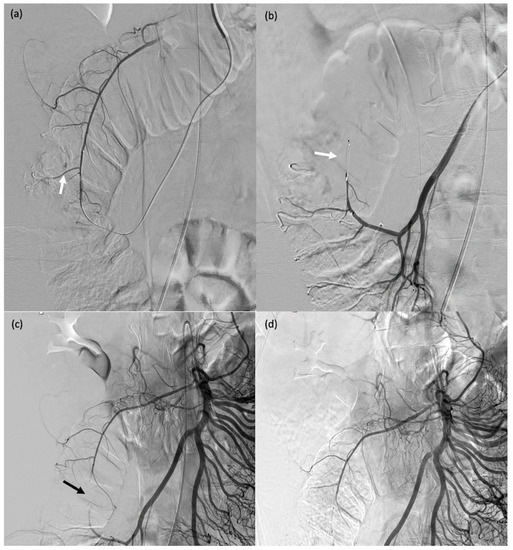

Figure 6. A 32-year-old female patient (#13) who passed blood per rectum 2 days after a right partial nephrectomy; computed tomography showed active bleeding from the right colon; due to haemodynamic instability, she was transferred to the operating room for emergent angiography. (a) Angiography showing contrast agent extravasation at the right colon (arrow). (bd) Catheterisation of the target arterial branch was not feasible and a single MVP-3Q was therefore used for sandwich embolisation of the right arterial trunk at the appropriate level (arrows).

Figure 7. A 71-year-old male (patient #11) with abdominal pain and haemodynamic instability. (a) Rupture of a false aneurysm of the posterior pancreaticoduodenal arcade (arrow). (b) Failure of initial catheterisation for MVP-3Q implantation due to angulation of the target artery (arrow). (c) Coil embolisation of the downstream branch (arrow). (d) Onyx™ embolisation of the aneurysmal sac and upstream branch (arrow).